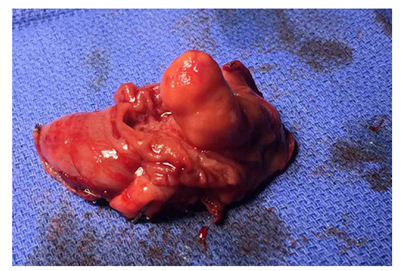

The small bowel lipoma was isolated on the jejunum and observed in active intussusception (Figure 2). The segment of intussuscepted jejunum was resected and re-anastomosed (Figure 3) without complications. The excised specimen was examined extracorporeally (Figure 4) before being sent for tissue evaluation by pathology. The gross specimen was consistent with CT imaging and revealed a 2cm subserosal lipoma. The resected bowel was incised on the back table to reveal an intraluminal lipoma adherent to the jejunal wall without evidence of necrosis or hemorrhage. Pathologic examination confirmed the diagnosis of a homogenous, subserosal lipoma of the jejunum (Figure 5).

Figure 4 Intaluminal view of resected gross specimen.